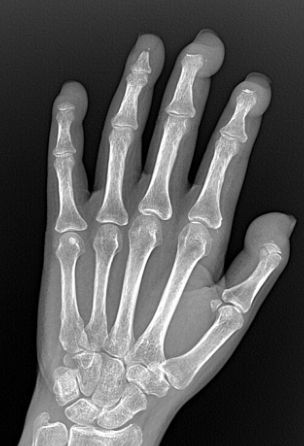

Consultant Rheumatologist 🩺, University Hospitals of Leicester NHS Trust. Loves Cricket 🏏.